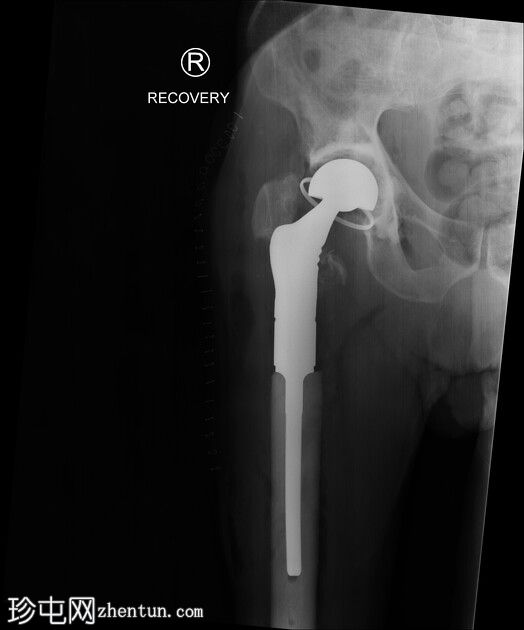

10.jpeg

正面

11.jpeg

患者随后接受了股骨近端置换术。

无金属部件损坏。